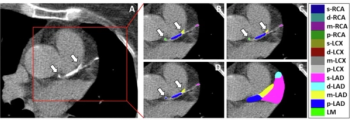

Through analysis of coronary computed tomography angiography (CCTA) images, the PlaqueIQ software provides quantification and classification of atherosclerosis, a common cause of myocardial infarction (MI) and ischemic stroke.